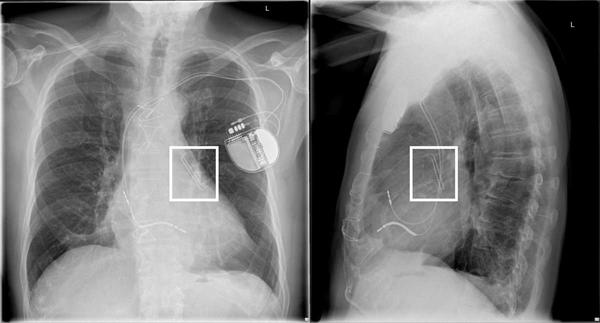

Abbildung 1: Röntgen-Thorax in 2 Ebenen, das AtriClip-Device zeigt sich in Projektion auf das LAA.